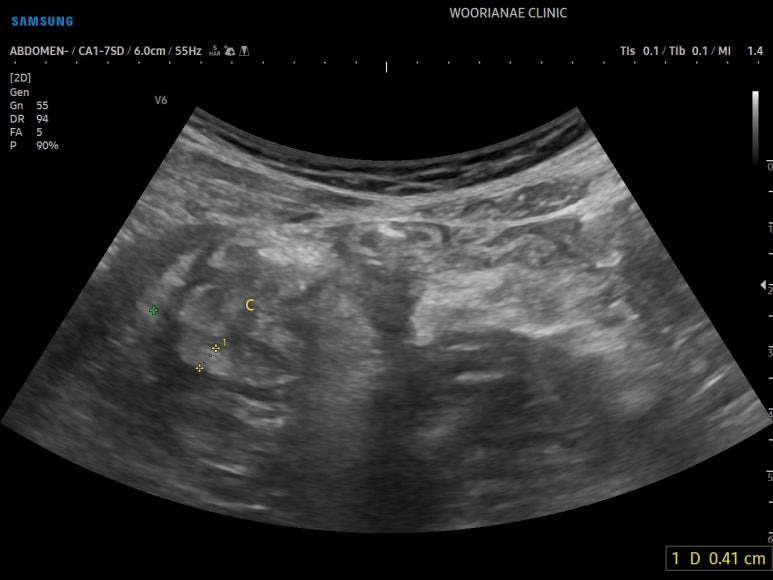

초음파 시행

회장 말단의 점막 비후가 의심되며

맹장 (cecum) 의 점막도 마찬가지 소견, 문제가 있는 것이다.

맹장의 점막 비후

컨벡스 프로브로 다시 조망해보면

게실 주변으로 염증성 지방변화가 장요근을 거의 타고 넘어가는 모습이다.